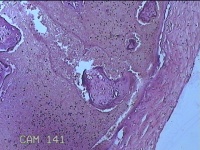

胎盘组织

胎膜早破 早产

停经36+1周,阴道流液3天。

灰白暗红色胎盘组织18x15.5x2.3㎝一个,表面光滑,血管清晰,颜色发暗,绒毛面结节状,轻度糜烂,表面有少许凝血块,切面见绒毛内有部分淤血,边缘蜕膜可见多个小血肿,脐带15x1.5x0.8㎝,切断脐带,见脐血管内有凝血块。